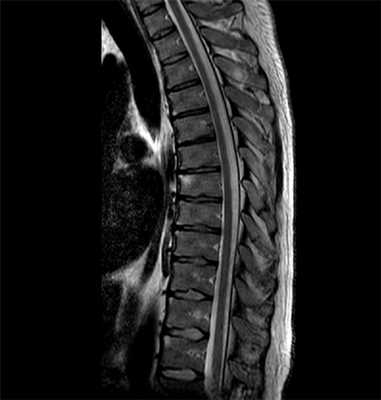

Исследования КПС и позвоночника у пациентов со СпА с помощью МРТ внесли большой вклад в понимание эволюции заболевания, ранней диагностики и были использованы в качестве объективного критерия оценки эффективности при клинических испытаниях. С внедрением этого метода появилась возможность диагностировать доструктурные изменения костной ткани, которые не выявлялись рентгенологическим методом, — ее воспаление (остеит) и дегенерацию (жировая дистрофия) [9]. Однако до настоящего времени неясна взаимосвязь воспаления костной ткани и прогрессирования ее структурных повреждений при аксСпА.

Методы, используемые в научно-исследовательской работе. Оценку клинической активности СпА и функционального статуса пациентов выполняли согласно общепринятым рекомендациям с использованием индексов ASAS. Для определения активности заболевания использовали индексы BASDAI (Bath Ankylosing Spondylitis Disease Activity Index) [13], ASDAS CРБ (Ankylosing Spondylitis Disease Activity Score) [13]. Функциональный статус оценивали по индексам BASFI (Bath Ankylosing Spondylitis Functional Index) и BASMI (Bath Ankylosing Spondylitis Metrology Index) [13]. Для оценки боли в спине, утренней скованности, глобальной оценки общего самочувствия пациентов, BASDAI и BASFI использовали числовую рейтинговую шкалу с числом баллов от 0 до 10. При подсчете болезненных энтезисов применяли индекс MASES (Maastricht Ankylosing Spondylitis Enthesitis Score) [13]. Помимо клинического обследования и стандартных лабораторных исследований (общий анализ крови, биохимический анализ крови, исследование уровня высокочувствительного СРБ) у всех пациентов определяли наличие HLA-B27, а также проводили обзорную рентгенографию костей таза и поясничного отдела позвоночника (ПОП) с захватом двух последних грудных позвонков (в боковой проекции). Всем пациентам проводили МРТ КПС и ПОП (на низкопольном аппарате Signa Ovation 0,35 Тесла, матрица 288×192). ПОП исследовали в сагиттальных проекциях, КПС — в полукоронарных. Активные воспалительные изменения (ВИ) определялись в режиме подавления жира (STIR) с толщиной срезов 4 мм. Выявление явного субхондрального отека костного мозга (остеита), визуализируемого как гиперинтенсивный сигнал в режиме STIR, расценивали в качестве признака спондилита, и/или СИ, и/или коксита. Наличие В.И. в КПС и позвоночнике констатировали в случае, если признаки остеита определялись как минимум на двух срезах или если выявлялось более двух гиперинтенсивных очагов активного воспаления на одном срезе. Для диагностики АС использовали модифицированные Нью-Йоркские критерии 1984 г. [1]. Для диагностики аксСпА применяли критерии ASAS для СпА с преимущественной аксиальной симптоматикой [8].